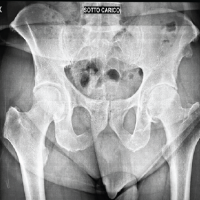

Due to the patient’s pathological fracture secondary to osteoporosis, a reinforcement screw was placed from the plate across her femoral neck and head to minimize the risk of future fracture in this area (Fig. 3c). The surgical wounds were closed with absorbable braided sutures for the subcutaneous tissues and nylon sutures for the skin. The patient was transferred to the recovery room in stable condition.